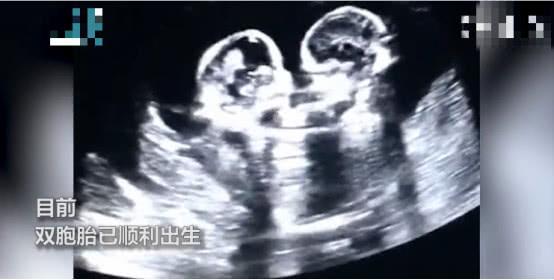

近日 , 网上有个搞笑的视频 , 引发大家的关注 。 视频中 , 宁夏银川的一女子怀了一对双胞胎姐妹 , 在宝宝3个月的时候 , 准时去医院做孕检 , B超显示两个宝宝竟然在妈妈肚子里打架 。

一开始是左边的宝宝先动手“打”了右边的宝宝一拳 , 右边宝宝随后立马“还击” , 两个宝宝就这样连续“战斗”了几个回合 , 这一幕引得医生和妈妈当场大笑 。 现在 , 这对双胞胎已经顺利出生 。